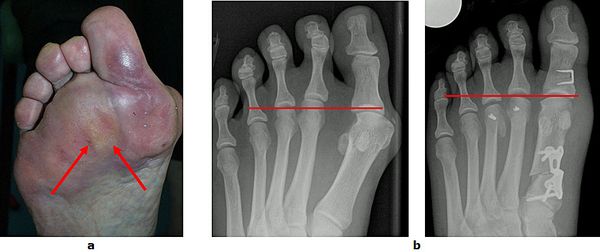

Abb.1: a Fortgeschrittene Hallux valgus Fehlstellung. Die Großzehe ist verdreht und verdrängt die zweite Zehe. Der Vorfuß ist verbreitert.

b Normaler Fuß

Individuelle Therapiekonzepte in der Behandlung des Hallux valgus (schmerzhafter Großzehenballen) ermöglichen die anatomische Rekonstruktion und die verlorengegangene Funktion wieder herzustellen. Alter und Aktivität der Patienten werden in der Behandlung berücksichtigt.